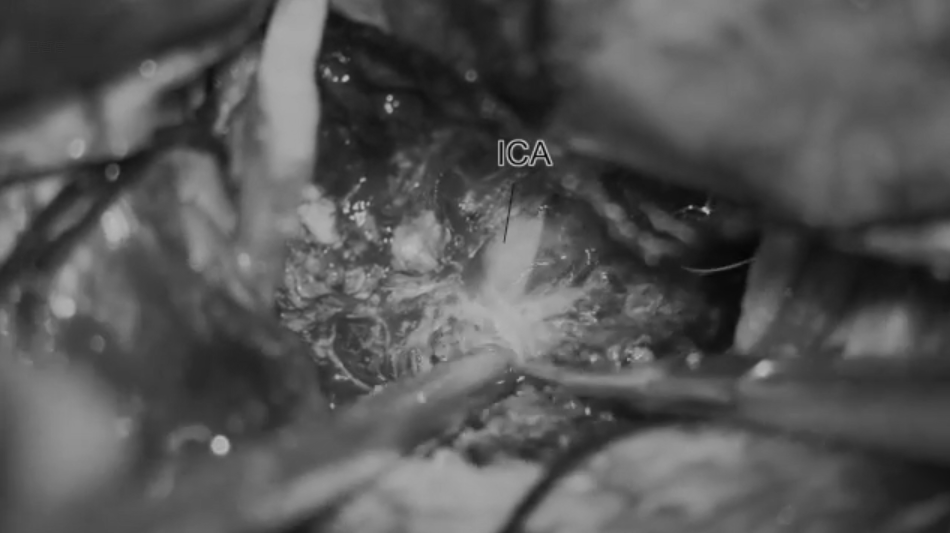

深入肿瘤后可见被包绕的颈内动脉;再向外下可见Liliequist膜及动眼神经。

显露后交通动脉;肿瘤额部可见钙化。进一步剥离并切除视神经周围肿瘤。将肿瘤自颈内动脉A1段剥离,可见颈内动脉分叉,以及内侧豆纹动脉受压。

肿瘤全切后,可见良好的视神经-颈内动脉三角及动眼神经三角,可见基底动脉、乳头体及垂体。